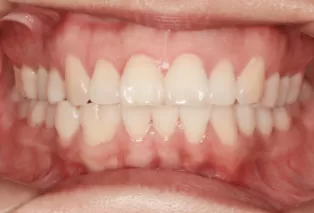

Photos intra-orales après traitement